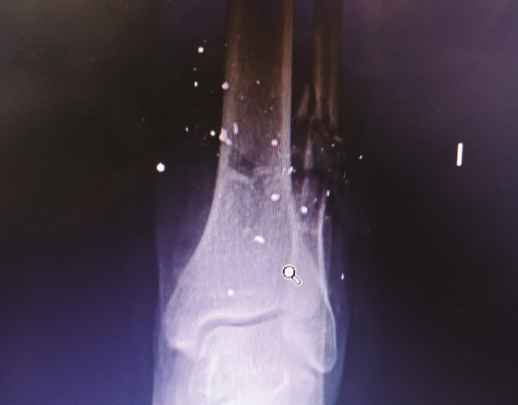

Se trata de un paciente varón de 49 años que presentaba una fractura abierta de peroné de tipo IIIB de Gustilo y Anderson tras sufrir un accidente por arma de fuego. Se observa defecto cutáneo de unos 10 cm en la región posterior de la pierna izquierda (Figuras 1A y 1B). En la radiografía se aprecia una fractura del tercio distal del peroné sin afectar a más estructuras óseas (Figura 2).

La fractura del peroné se trató de forma conservadora (Figura 4).

Figura 2. Radiografía tomada en urgencias. Se aprecia fractura del tercio distal del peroné con conminución ósea.